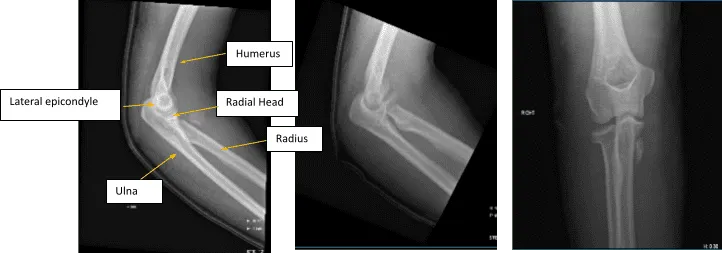

Figure 1. AP Oblique and Flexion Lateral Projection of Right Elbow

Hemarthrosis and a comminuted, affected, acute radial head fracture is present. The plantar-medial portion of the proximal shaft of the right ulna is home to a fracture fragment that has been severely misaligned. Though no donor defect is visible, this could be a fragment of the radial head that has been significantly displaced. A second fracture site is also a possibility.